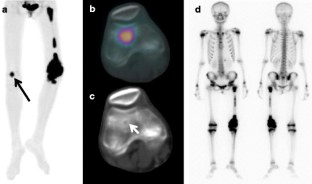

Fig. 1

Fig. 2

Fig. 3

Fig. 4

Fig. 5

Fig. 6